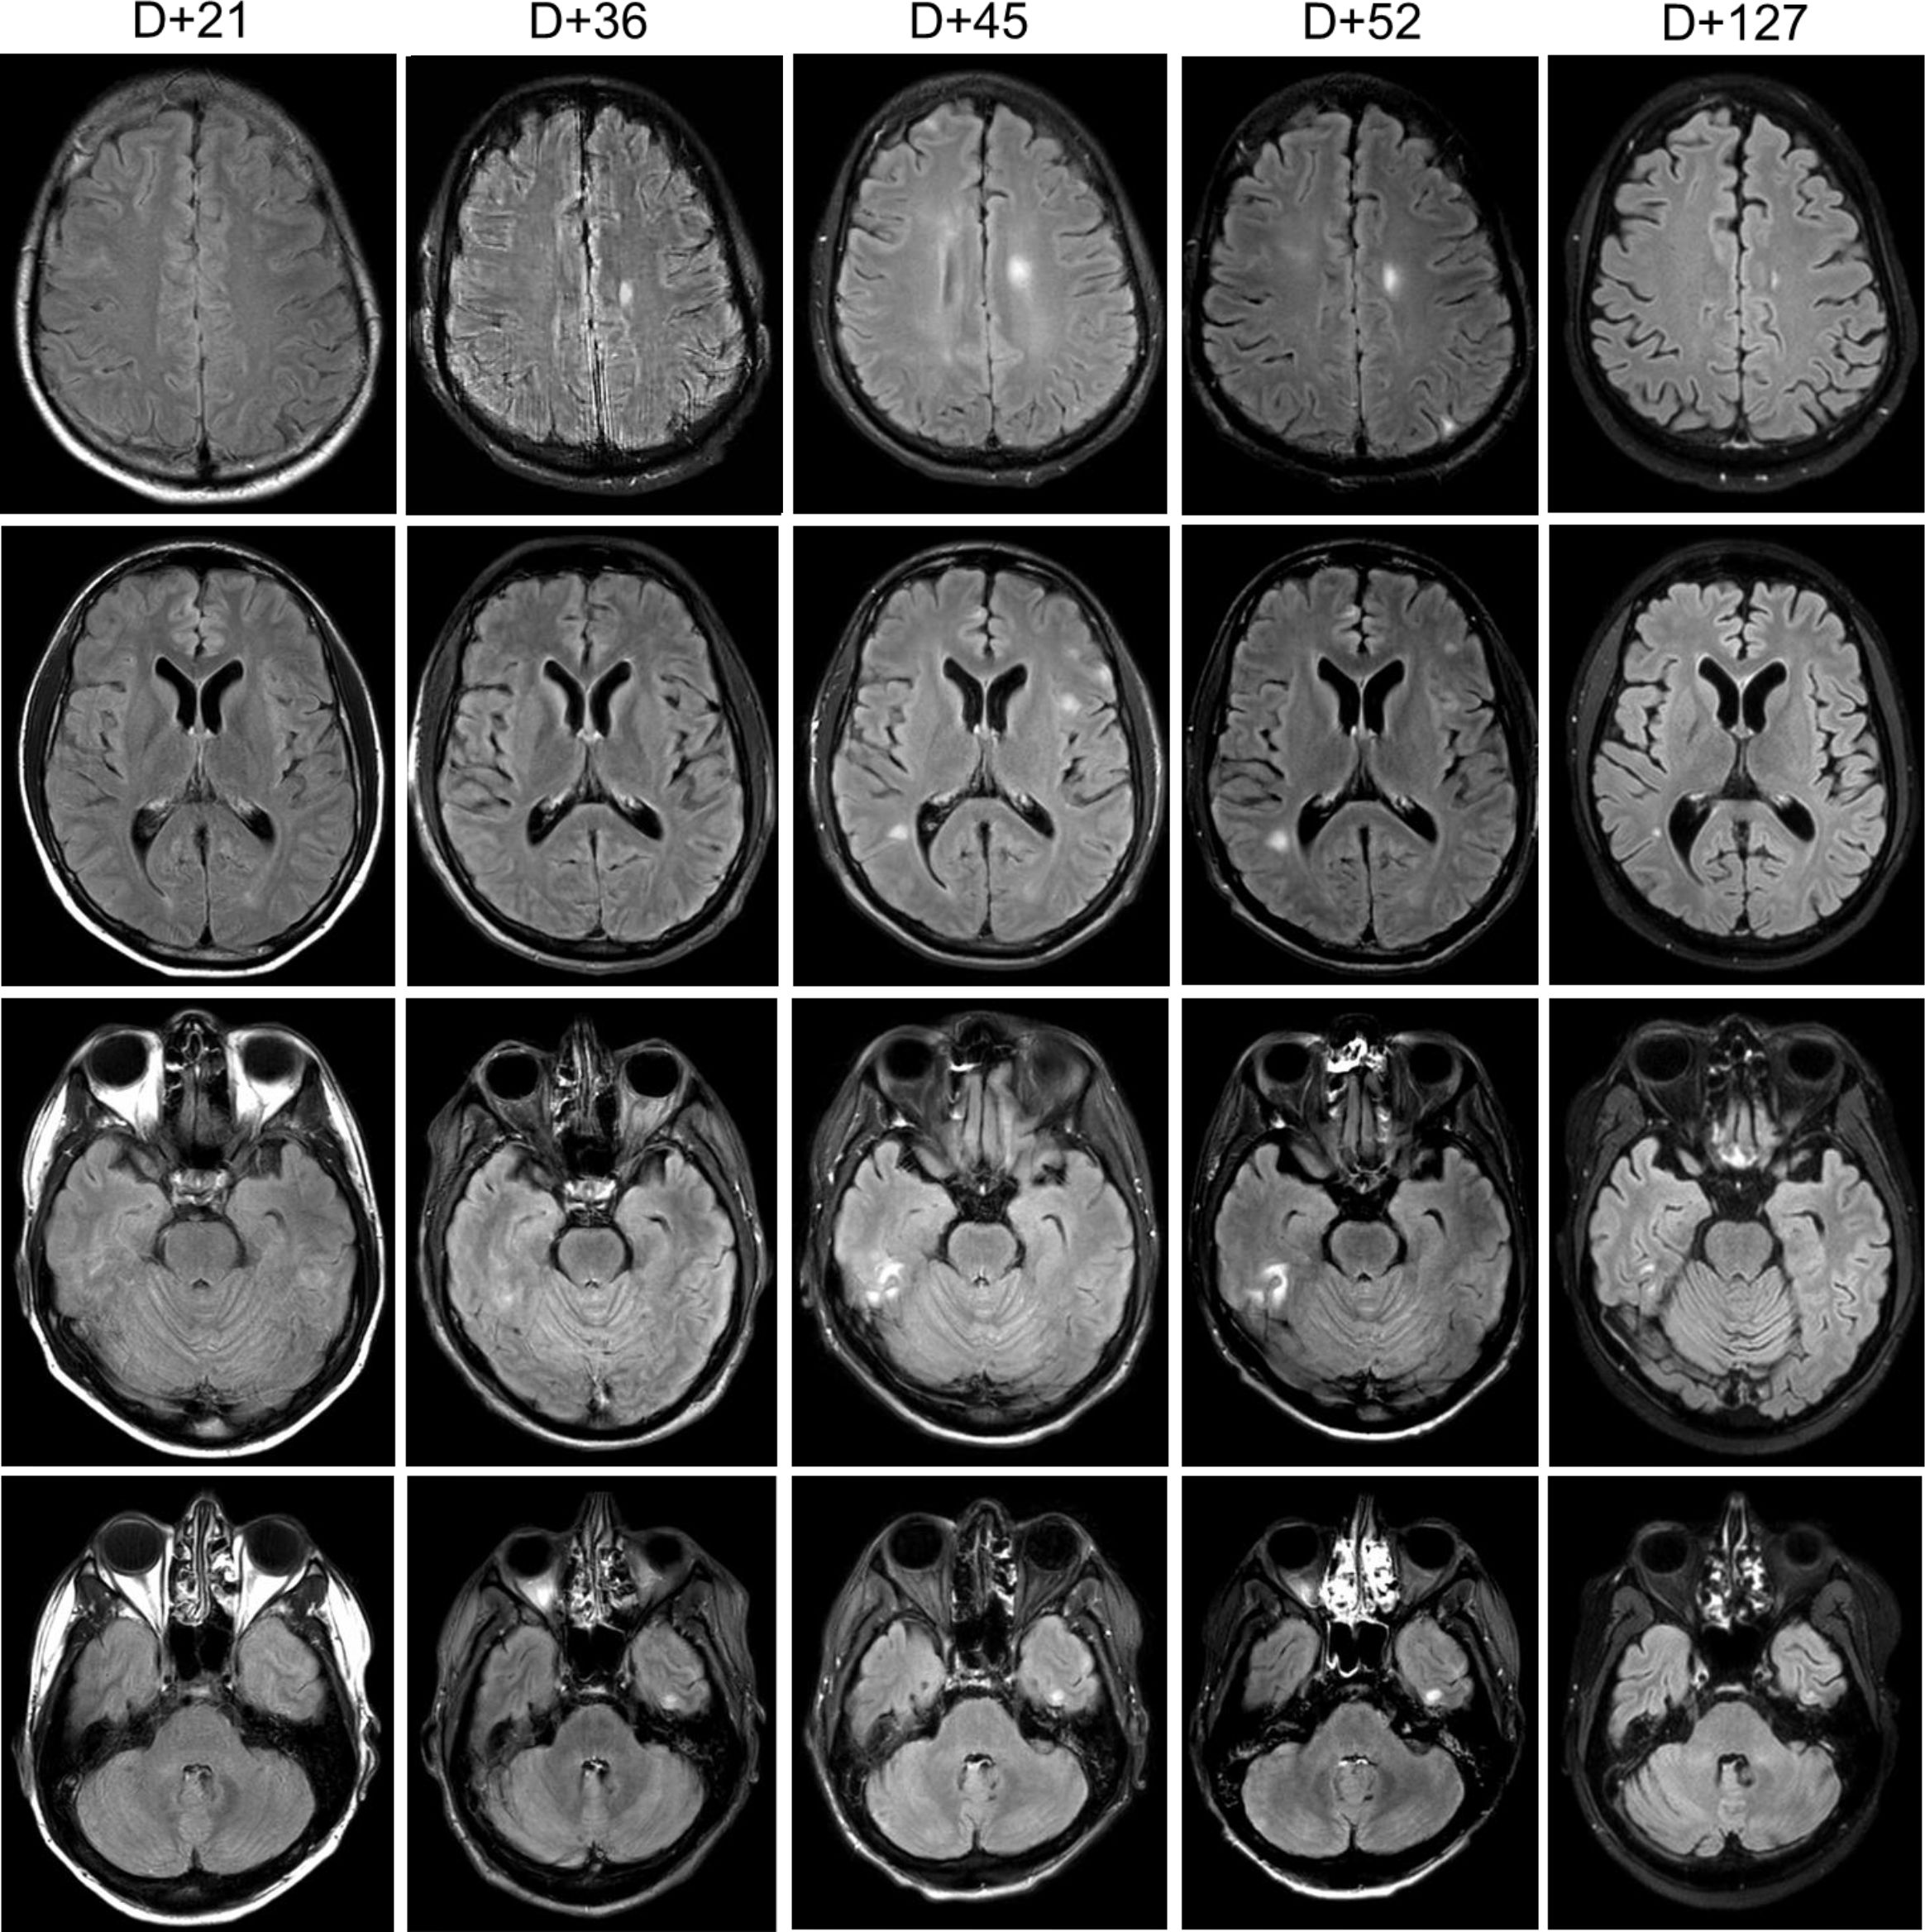

Epstein-Barr virus (EBV) associated encephalitis is seen in patients who have undergone allogeneic hematopoietic stem cell transplant and can be associated with significant morbidity and mortality. The mainstay of treatment has been antiviral therapy with nucleoside analogues and reduction of immunosuppression. Here we describe an adult patient diagnosed with refractory EBV-associated encephalitis within 30 days post-allogeneic transplant successfully treated with intrathecal rituximab, which to our knowledge is the first case treated in this manner.